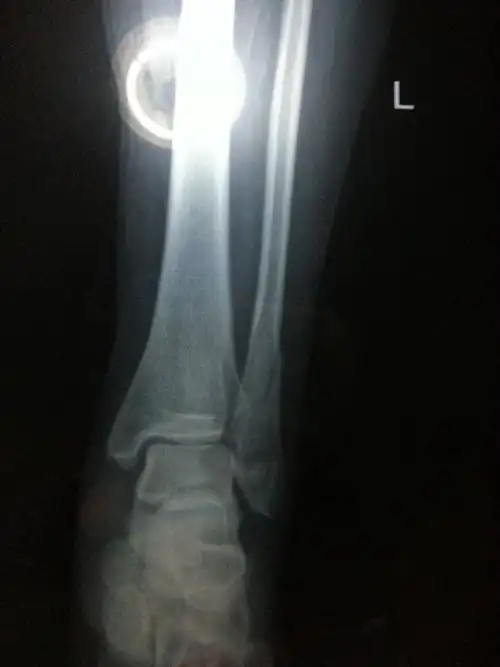

我是二月五号左脚脚踝腓骨骨裂到现在已经卧床六个星期了.